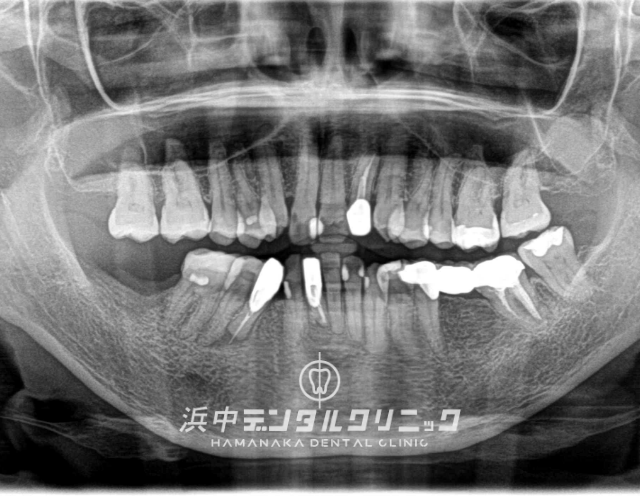

BEFORE

AFTER

患者様の主訴

下の両方の奥歯が割れたので噛めるようにしたい。

診断結果

日常的に強い歯ぎしりをしてる患者様で下顎左右の7番目の歯が歯根破折をしてました。

治療内容

下顎左右両側の7番目の歯を抜歯後にインプラントを埋入して仮歯を経て最終上部構造(ジルコニアセラミック)をスクリュー固定しました。

治療後経過

インプラント治療終了後から約3年経過していますが全く問題なく経過良好です。

| 治療期間 | 約7ヶ月 |

|---|---|

| 治療にかかった費用 | インプラント体(フィスクチャー308,000円)×2本 +インプラント土台(アバットメント77,000円)×2本 +インプラント人工歯(上部構造ジルコニアセラミック165,000円)×2本 +静脈内鎮静麻酔77,000円+仮歯代22,000円×2本分 +サージカルステント55,000円 =合計1,276,000円 |

| リスク副作用 | インプラントは入れたら終わりではなく、きちんとメンテナンスしないと歯周病になることもあるので、定期的にクリーニングや噛み合わせの調整が必要です。 |